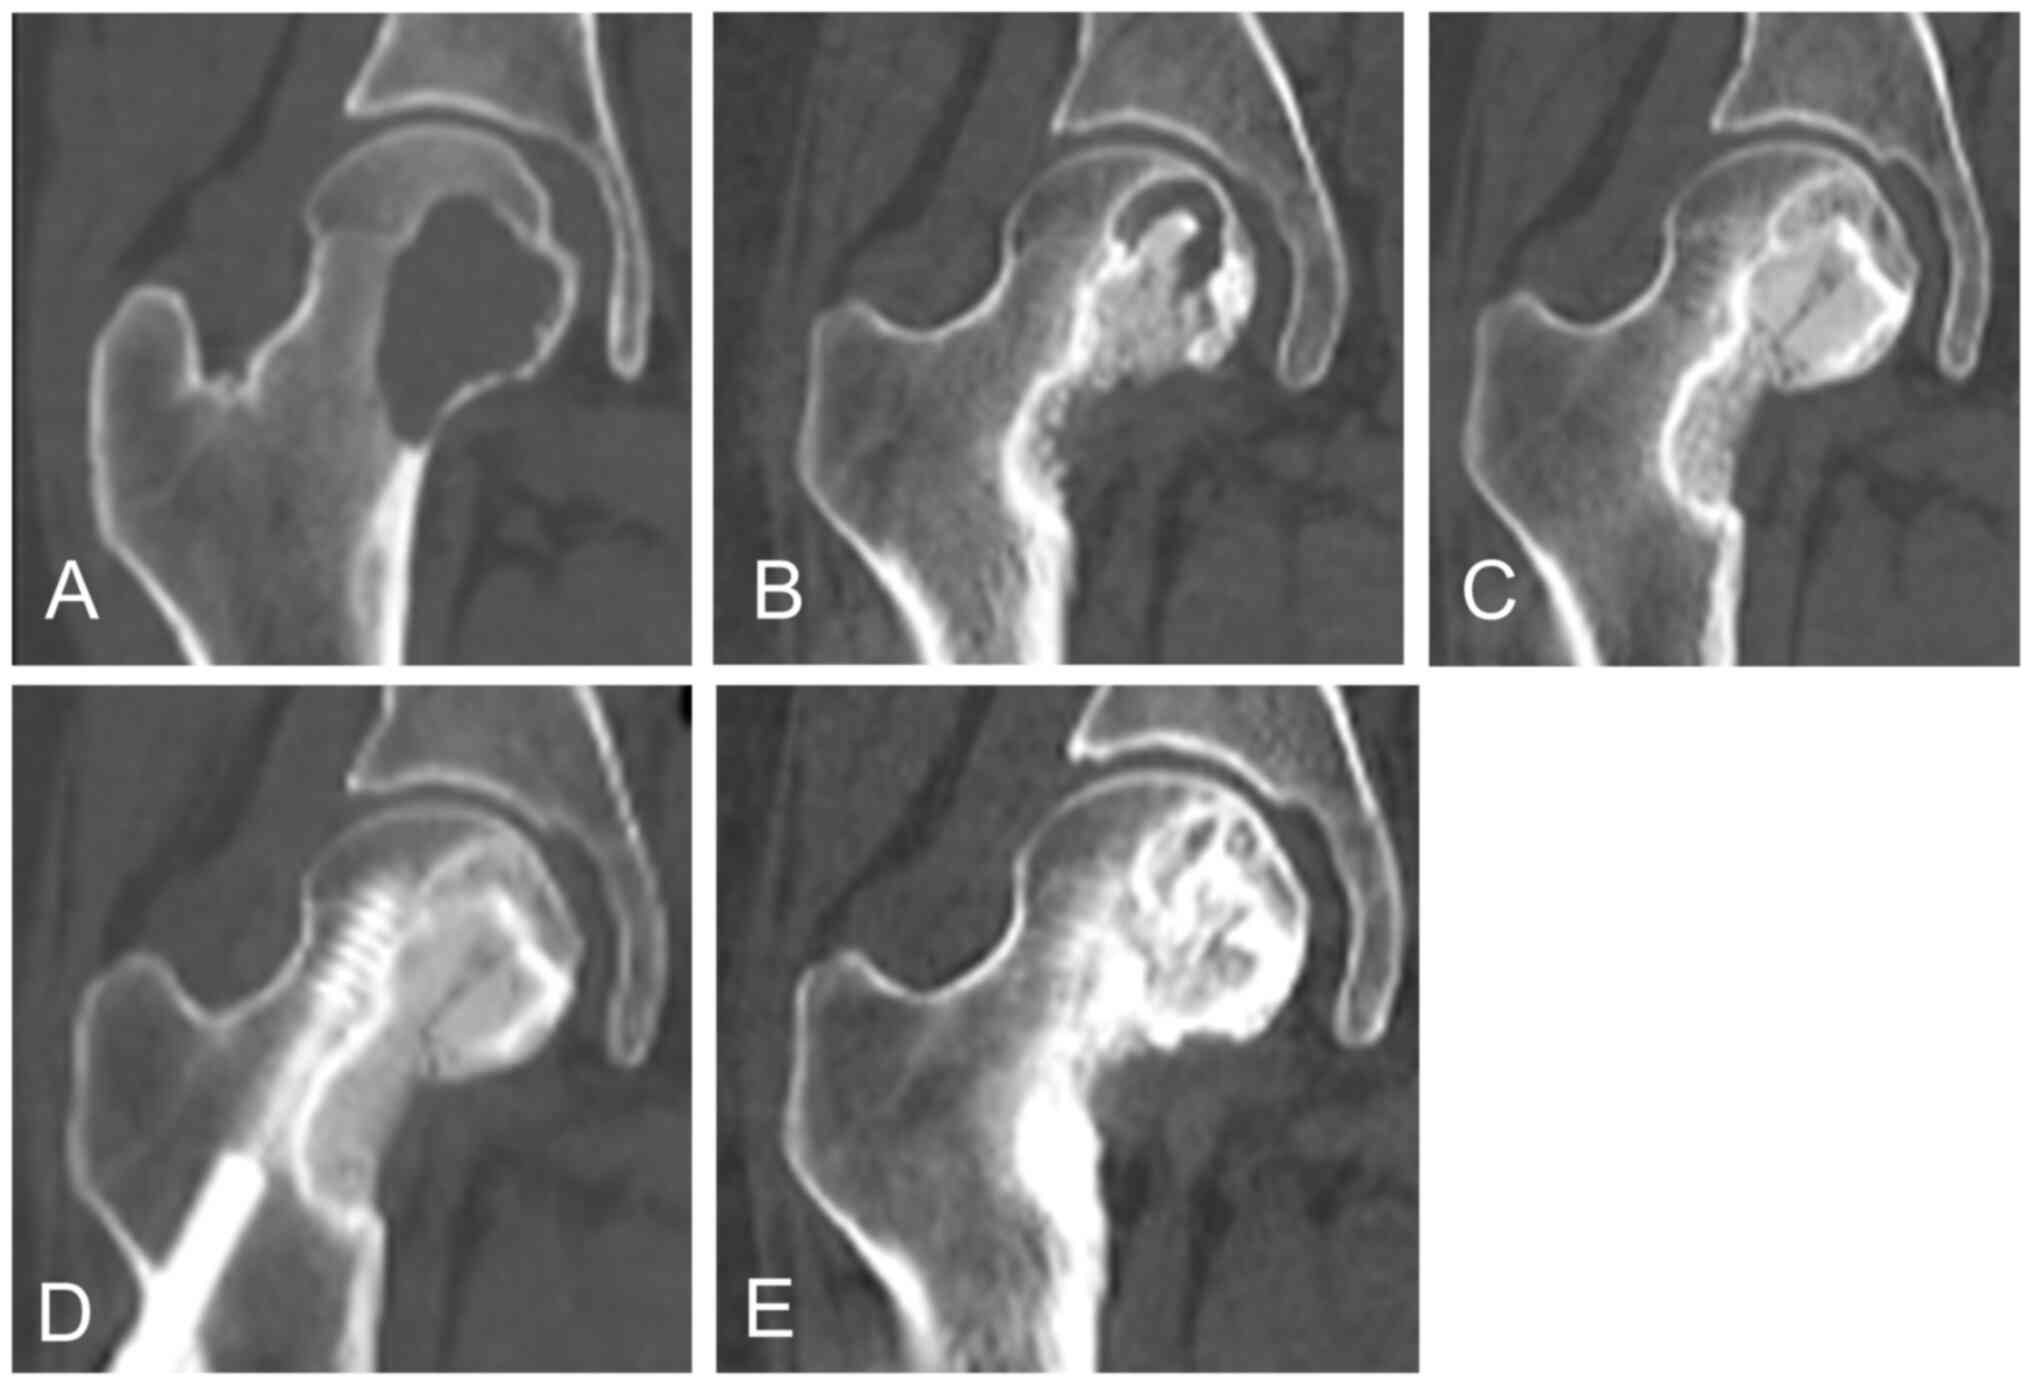

A 26-year-old woman had GCTB of the femoral head. CT images (Fig. 4A) showed a lytic lesion. She underwent two rounds of curettage and bone grafting with internal fixation. CT revealed a lytic lesion in the femoral neck (Fig. 4B). Hence, denosumab was initiated. After 4 months, a change in sclerosis was observed (Fig. 4C). After 10 months, the lytic lesion was completely filled with newly formed bone (Fig. 4D). Denosumab was administered every 24 weeks. At the last follow-up, the patient showed stable disease (Fig. 4E).

A 26-year-old woman with GCTB in the femoral head. (A) CT images showed a lytic lesion. She underwent two rounds of curettage and bone grafting with internal fixation. (B) CT image showed a lytic lesion in the femoral neck. (C) Denosumab treatment was initiated. After 4 months, sclerosis change was confirmed. (D) After 10 months, the lytic lesion was filled with newly formed bone. Then, 24-weekly denosumab treatment was administered. (E) At the last follow-up, the patient showed stable disease. GCTB, giant cell tumor of bone; CT, computed tomography.